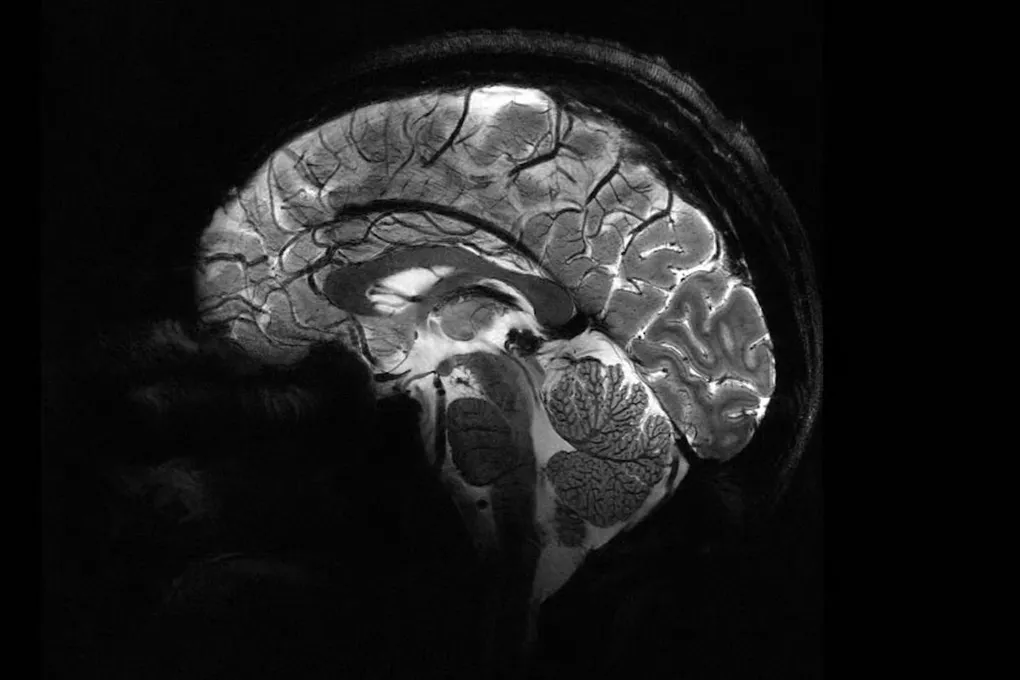

Представьте, что вы можете разглядеть мозг с такой детализацией, будто изучаете карту города с высоты птичьего полёта. Это стало реальностью. Самый мощный в мире МРТ-сканер, Iseult, наконец-то заглянул в человеческий мозг. Полученные изображения — не просто красивые картинки. Это окно в будущее нейронауки, где мы сможем расшифровать тайны сознания и найти ключи к лечению болезней Альцгеймера и Паркинсона.

От тыквы к человеку: долгий путь к первому скану

Сначала были тыквы. Да-да, несколько лет назад гигант тестировали на овощах. Но теперь его «пациентами» стали 20 здоровых добровольцев. Результат? Снимки, от которых захватывает дух. Они открывают нам детали, которые раньше были скрыты: как мозг кодирует мысли, какие нейронные «подписи» соответствуют самому феномену сознания. Мы стоим на пороге величайшей загадки — и у нас появился инструмент, чтобы её разгадать.

Но Iseult — не просто философский инструмент. Его практическая миссия — борьба с нейродегенеративными заболеваниями. Он способен улавливать слабые химические сигналы, невидимые для обычных томографов: концентрацию глюкозы, глутамата, лития. Нарушения в их балансе — ранние признаки глиом, Альцгеймера или Паркинсона. Теперь мы можем их увидеть. А значит, и остановить болезнь на подступе.